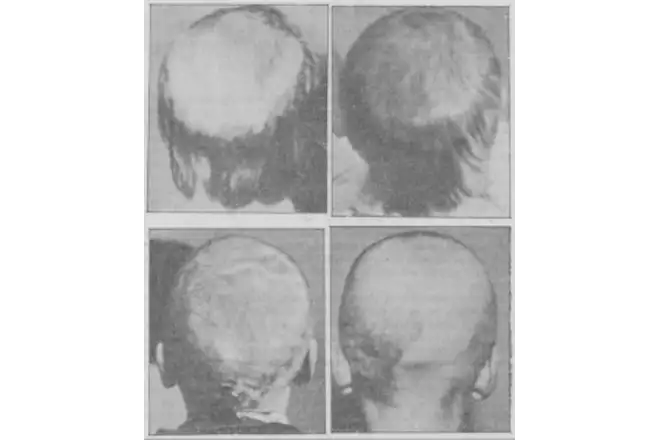

X射线治疗头癣的原理十分简单:利用辐射破坏毛囊,使感染的头发自然脱落,然后再让新发长出。这种方法在理论上比手动拔发更加高效,也相对无痛。1907年,奥地利放射学家罗伯特·金伯克和英国医生霍雷肖·亚当森共同制定了一套标准化的治疗方案,被称为亚当森-金伯克方案。按照这个方案,患者需要接受数次X光照射,每次照射后等待约三周时间让头发完全脱落。随后,医生会在头皮上涂抹抗菌药膏,用特制的蜡帽覆盖头部,防止真菌再次感染。整个过程通常持续约二十一天。

治疗的后果是灾难性的。儿童们在照射后立即出现急性辐射反应:恶心、呕吐、头痛和头皮灼痛。在回家的路上,许多孩子吐得一塌糊涂。几天后,头发开始脱落,头皮出现红斑和水泡。对于大多数儿童来说,这些症状会在几周内消退,新的头发会长出来。但对于一小部分不幸者——估计约百分之五至百分之十——辐射造成的伤害是永久性的。他们的头皮留下了无法愈合的溃疡,颅骨发育受到影响,更严重的是,辐射正在悄悄地改变他们细胞的DNA。